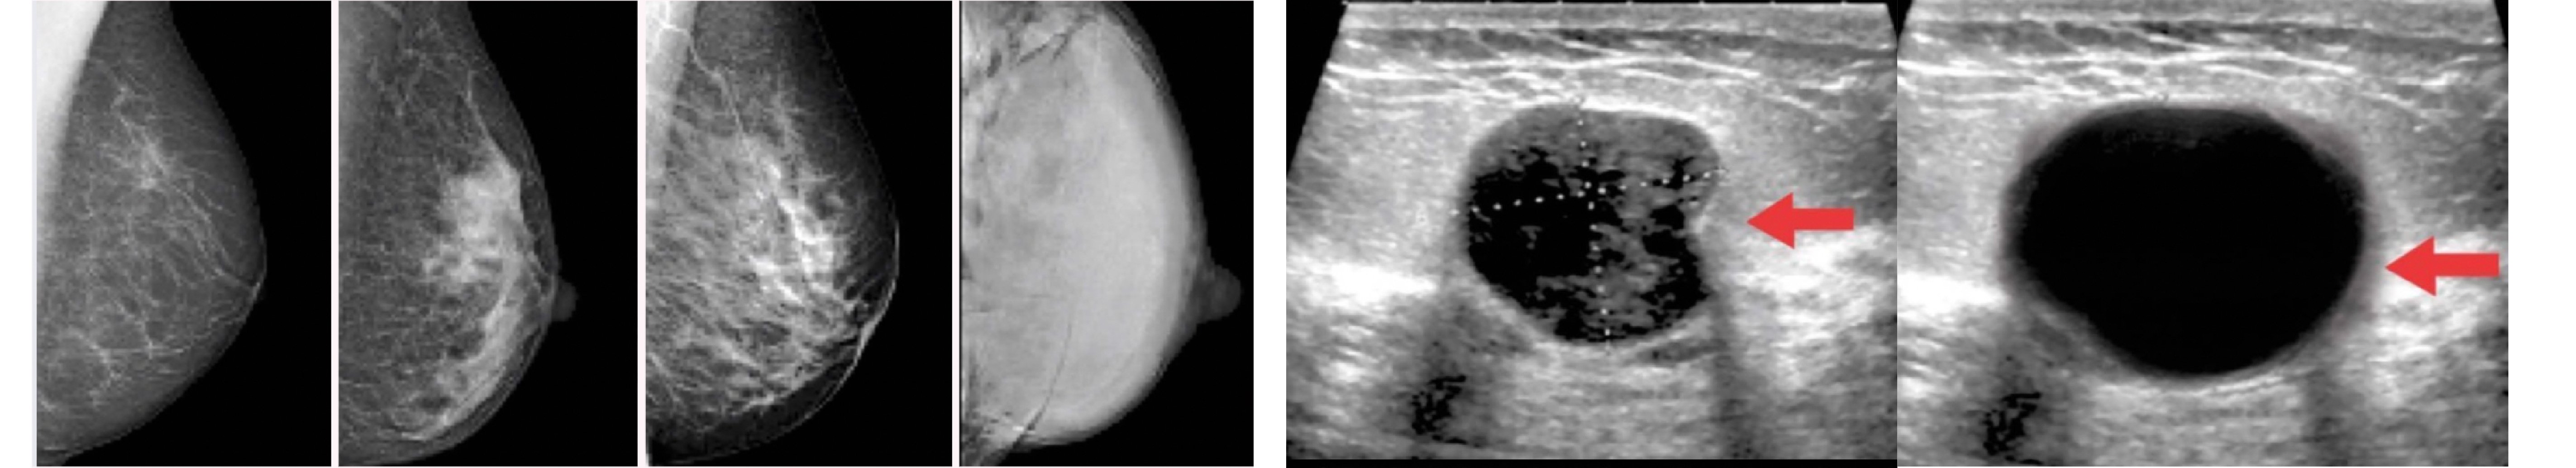

Ecografía

La ecografía usa ondas de sonido (no radiación) para ver el interior de la mama con más detalle. Generalmente se usa cuando:

- La mamografía mostró algo que hay que mirar mejor

- Se palpó un bulto en el examen físico

Este examen ayuda a saber si un bulto es sólido, lleno de líquido (quiste) o mixto. Lo que es clave para decidir qué hacer después.

Mamografia y ecografia mamaria.